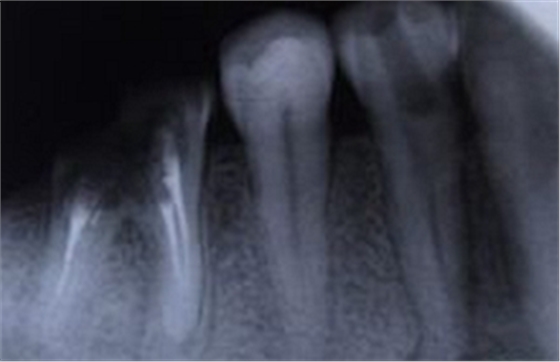

其面积为3×4平方厘米。一张牙片可以显示3-4个牙齿。牙齿在牙片上显示出白色阻射影像。其中牙釉质阻射最强,牙本质和牙骨质阻射低于牙釉质。牙髓腔呈黑色透明影像,根管口至根尖孔呈逐渐变细的影像。

由于牙根的牙髓组织发炎,引起牙根尖组织病变,如根尖牙周膜腔增宽、根尖囊肿等病变均可在牙片上显示出来。

①了解病牙根管情况:如根管数目、粗细、弯曲度以及有无钙化、有无内吸收等情况。

③检查治疗情况:如牙片显示根管充填是否到底或有无超填。